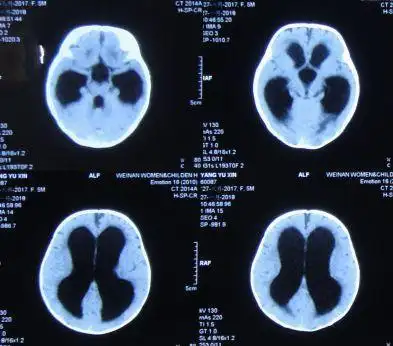

广州医科大学附属第五医院 病例分享:婴幼儿脑积水病例分享

落日征 脑积水